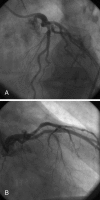

Patients and methods: The Primary Angioplasty in patients transferred from General community hospitals to specialized PTCA Units with or without Emergency thrombolysis-1 (PRAGUE-1) and PRAGUE-2 studies enrolled 1150 patients with ST-elevation acute myocardial infarction, in whom 625 coronary angiograms were performed within 2 h of the initial electrocardiogram. A simultaneous registry included an additional 379 coronary angiograms performed during the ST-elevation phase of a suspected myocardial infarction. Thus, a total of 1004 angiograms were retrospectively analyzed. A normal coronary angiogram was defined as one with the absence of any visible angiographic signs of atherosclerosis, thrombosis or spontaneous spasm.

Results: Normal coronary angiograms were obtained for 26 patients (2.6%). Among these, the diagnosis at discharge was a small myocardial infarction in seven patients (0.7%), acute (peri)myocarditis in five patients, dilated cardiomyopathy in four patients, hypertension with left ventricular hypertrophy in three patients, pulmonary embolism in two patients and misinterpretation of the electrocardiogram (ie, no cardiac disease) in five patients. Seven patients with small infarctions underwent angiography within 30 min to 90 min of complete relief of the signs of acute ischemia, and thus, angiograms during pain were not taken. None of the 898 patients catheterized during ongoing symptoms of ischemia had a normal coronary angiogram. Spontaneous coronary spasm as the only cause (without underlying coronary atherosclerosis) for the evolving infarction was not seen among these 898 patients. Thus, the causes of the seven small infarcts in patients with normal angiograms remain uncertain.

Conclusions: The observed prevalence of normal coronary angiography in patients presenting with acute chest pain and ST elevations was 2.6%. Most of these cases were misdiagnoses, not infarctions. A normal angiogram during a biochemically confirmed infarction is extremely rare (0.7%) and was not seen during the ongoing symptoms of ischemia.